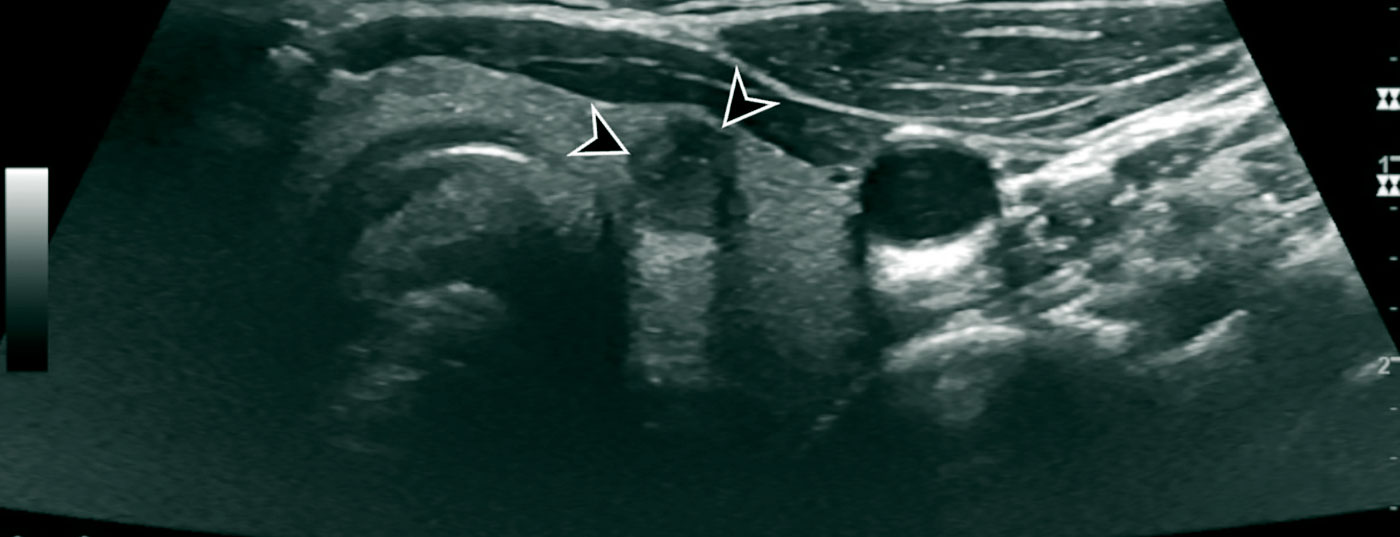

Schilddrüsenkarzinome können dank moderner bildegebender Verfahren heute gut diagnostiziert werden und haben häufig eine gute Prognose. Die postoperative Risikostratifizierung sollte aber an einem Zentrum mit dezidiertem Schilddrüsenboard stattfinden.